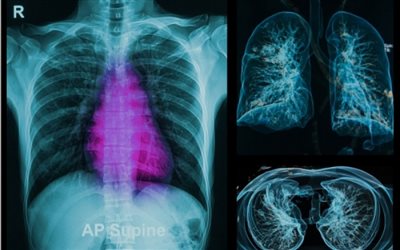

Εξετάσεις με ακτινοβολία: Πόσο αυξάνονται οι πιθανότητες καρκίνου

Τα τελευταία χρόνια αυξάνονται σταθερά οι απεικονιστικές εξετάσεις που γίνονται με τη χρήση ακτινοβολίας.